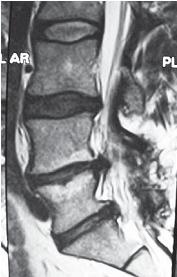

На МРТ №°103 наблюдается грыжа межпозвонкового диска в сегменте LIV-LV, частично компенсированная спондилёзом, гипертрофия задней продольной связки и выраженный эпидурит на данном уровне. В сегменте LV-SI наблюдается протрузия межпозвонкового диска, компенсированная спондилёзом. На уровне этих же сегментов наблюдается рубцовоспаечный процесс, как следствие перенесённой хирургической операции — ламинэктомии, проведённой в сегментах (LIV-LV, LV-SI), с целью устранения грыжи межпозвонковых дисков и декомпрессии спинномозговых корешков на данных уровнях. Приведённый ниже случай является показательным примером, как пациентка попала к недобросовестному хирургу, который сделал ей абсолютно необоснованную операцию. ![]() На МРТ № 104 наблюдается начальная стадия дегенеративного процесса в шейном отделе позвоночника, протрузия межпозвонкового диска в сегменте CVI—CVII. На МРТ № 105 наблюдается состояние после проведённой тотальной дискэктомии с передним межтеловым спондилодезом в сегменте CV—CVII, выпрямление физиологического лордоза, абсолютный стеноз спинномозгового канала с блоком ликворных путей, секвестрированные грыжи (с краниальной миграцией секвестров) в сегментах CIV-CV, CV-CVI, CVII-ThI. Состояние пациентки после операции ухудшилось, а в течение последующего года — значительно усугубилось. В данном конкретном случае не совсем понятно, зачем сделали эту операцию? Дооперационные жалобы больной были больше сосудистого характера. Прямых показаний к операции просто не было! Если бы данная пациентка прошла медикаментозное лечение у невропатолога, без хирургического вмешательства, то сейчас её здоровье было бы намного лучше, да и будущее бы не вызывало опасений в плане последующих осложнений. Вот ещё трагический случай во время проведения необоснованной операции. ![]() На МРТ № 106 состояние шейного отдела пациентки до операции. Наблюдается сглаженность физиологического лордоза, ликворные пути свободны, компенсированные протрузии межпозвонковых дисков в сегментах СIII—СIV На МРТ № 107 состояние шейного отдела той же пациентки после дискэктомии с межтеловым спондилодезом в сегменте CV—CVI, кроме того наблюдается травма спинного мозга на данном уровне хирургической фрезой. Если до операции у данной пациентки были незначительные вертебробазилярные нарушения, то после… Травма спинного мозга хирургической фрезой — это, конечно, трагическая случайность. Ведь от ошибок никто не застрахован и добросовестный врач никогда не даст гарантии на положительный исход любого вида лечения. Но в данном случае проведение самой операции было абсолютно необоснованным, фактически она превратила нормального человека в инвалида. Следующий пример также демонстрирует, какие бывают последствия после дискэктомии с межтеловым спондилодезом. |